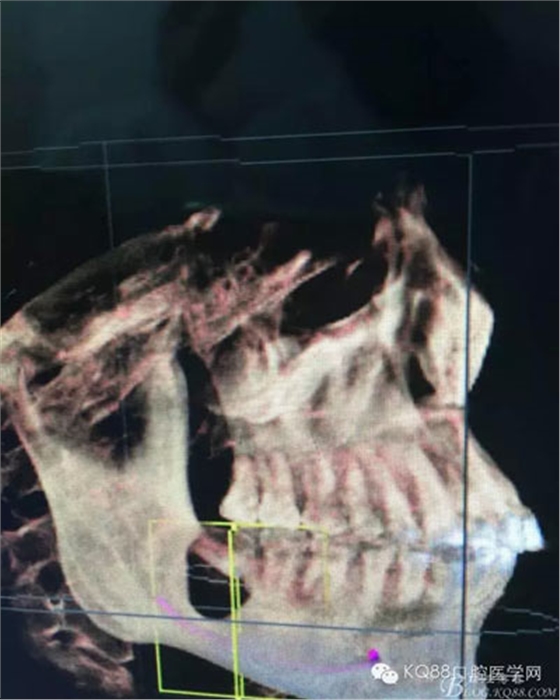

圖4.三維重建也提示:48拔除難度不大